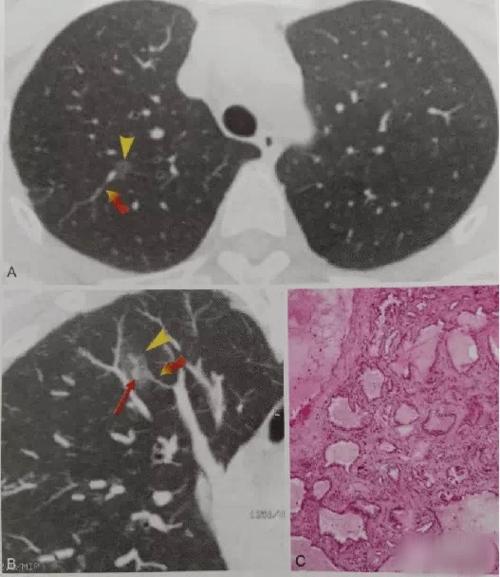

肺结节读片(12):容易忽视的囊腔样肺腺癌的ct特点

早期肺癌ct图 图解